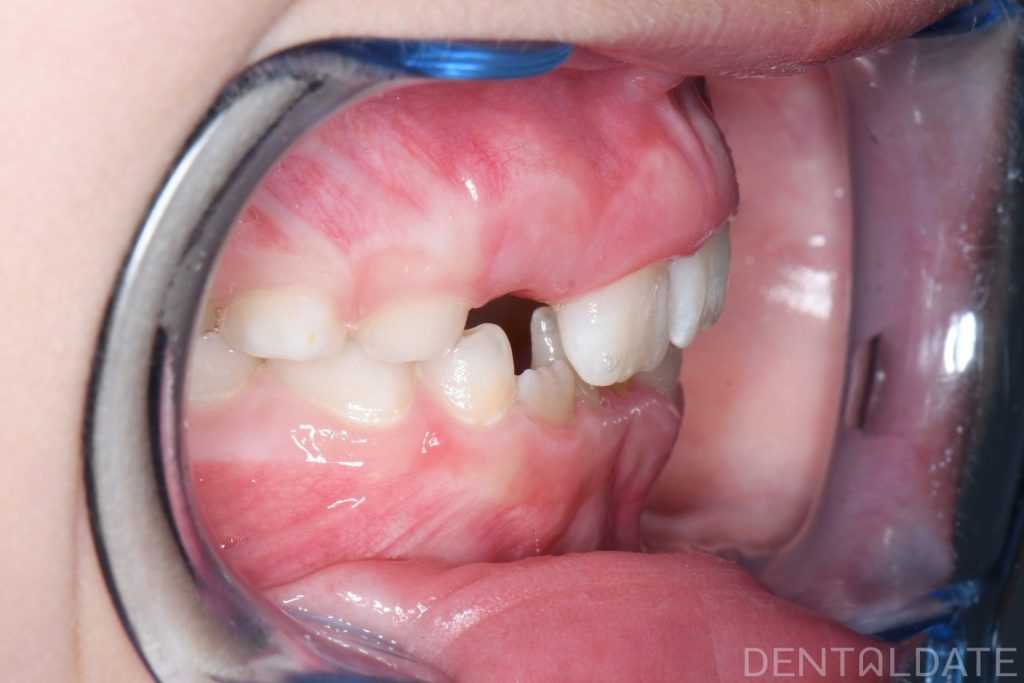

Parents sought an orthodontic consultation due to concerns about the aesthetics of their child’s smile.

To achieve harmony between function and aesthetics, a Haas appliance was used, followed by a myofunctional appliance.